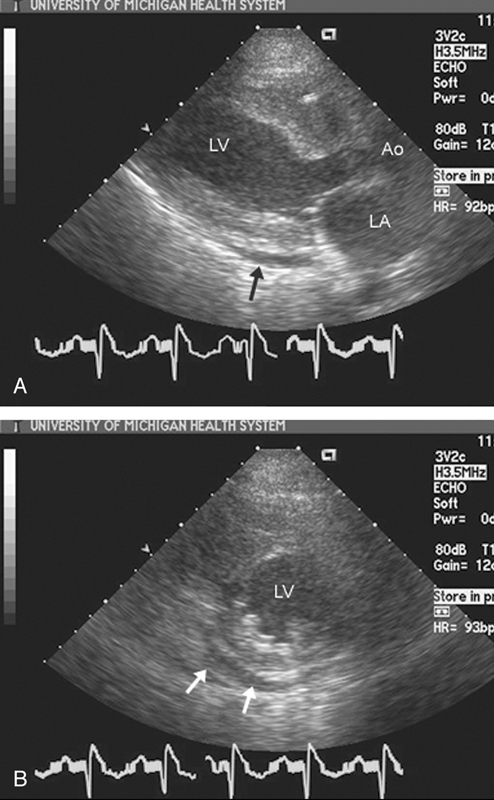

فحوصات تشخيصية لبعض امراض القلب والشرايين التاجية